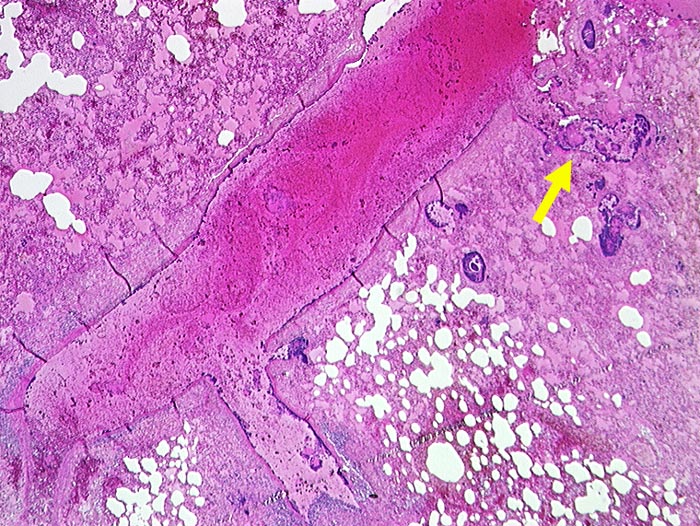

Blaue Bakterienhaufen in einem Pulmonalarterienast und im angrenzenden Lungenparenchym. Lungenödem und Hämorrhagien.

Septische Embolien in der Lunge. Nachweis koagulasepositiver Staphylokokken im Blut und im Perikarderguss.